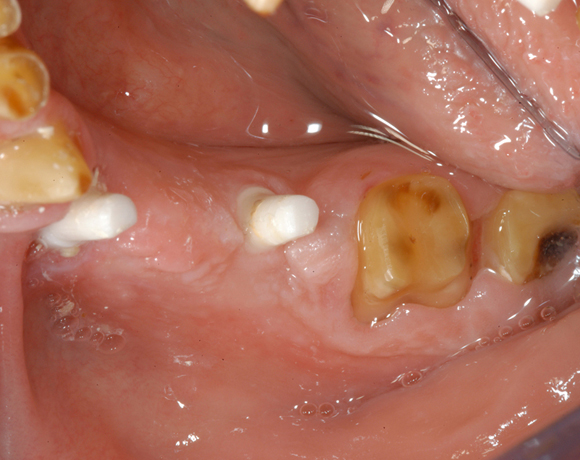

6 Implantate und viele Kronen und Brücken

Mit dem zweiteiligen vollkeramischen Implantat lassen sich auch große Lücken überbrücken.

Im vorliegenden Patientenfall waren die Zähne 11 – 26 mit einer provisorischen Brücke versorgt, der Patient konnte damit aber nicht essen. Auch im Unterkiefer waren die vorhandenen Kronen und Brücken insuffizient. Es wurde eine komplette Neuversorgung für Ober- wie Unterkiefer geplant.